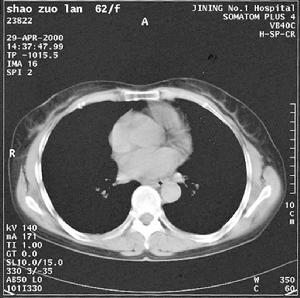

觀察

肉眼觀察,非細菌性血栓性心內膜炎,非感染性心內膜炎

惡性腫瘤肉眼觀察,非細菌性血栓性心內膜炎

這又是一個位於最右方尖端的消耗性贅生物,這類贅生物的大小雖然很少超過0.5厘米,但是非常容易形成栓塞。